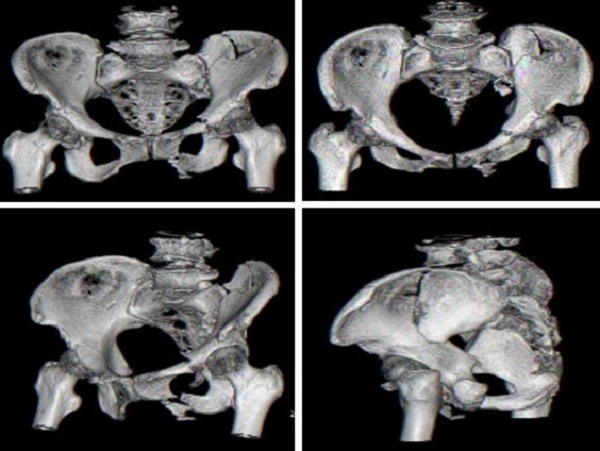

術(shù)前CT檢查:

近日,二一五醫(yī)院骨科醫(yī)院創(chuàng)傷骨科收治了一例54歲女性骨盆骨折患者,查體發(fā)現(xiàn)左髖關(guān)節(jié)因疼痛活動受限,骨盆擠壓分離試驗(+),X線及CT檢查提示骨盆骨折,骨盆骨折Young & Burgess 分型為LC—II型骨折,術(shù)前經(jīng)左下肢骨牽引,手法協(xié)助閉合復(fù)位拍片可見骨盆骨折復(fù)位良好,郭永良主任醫(yī)師詳細了解患者受傷機制,根據(jù)復(fù)位效果及骨折類型制定了微創(chuàng)化手術(shù)治療方案,即 LC-Ⅱ通道螺釘+恥骨髓內(nèi)針的微創(chuàng)化治療。